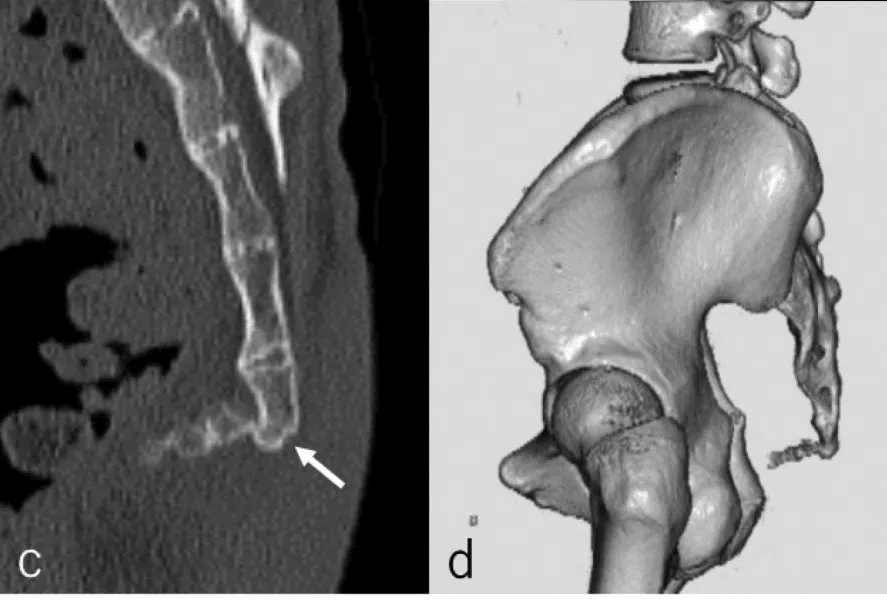

また、尾骨の形態や可動性も尾骨痛に関与します。過度な屈曲・伸展、側方偏位、骨棘形成などがリスクとなることが報告されています。

尾骨は骨盤底筋群や靱帯が付着する部位であるため、これらの緊張や不均衡が尾骨痛を助長する可能性もあります。近年では、海外における経直腸的なオステオパシー手技療法の有効性も報告されています。